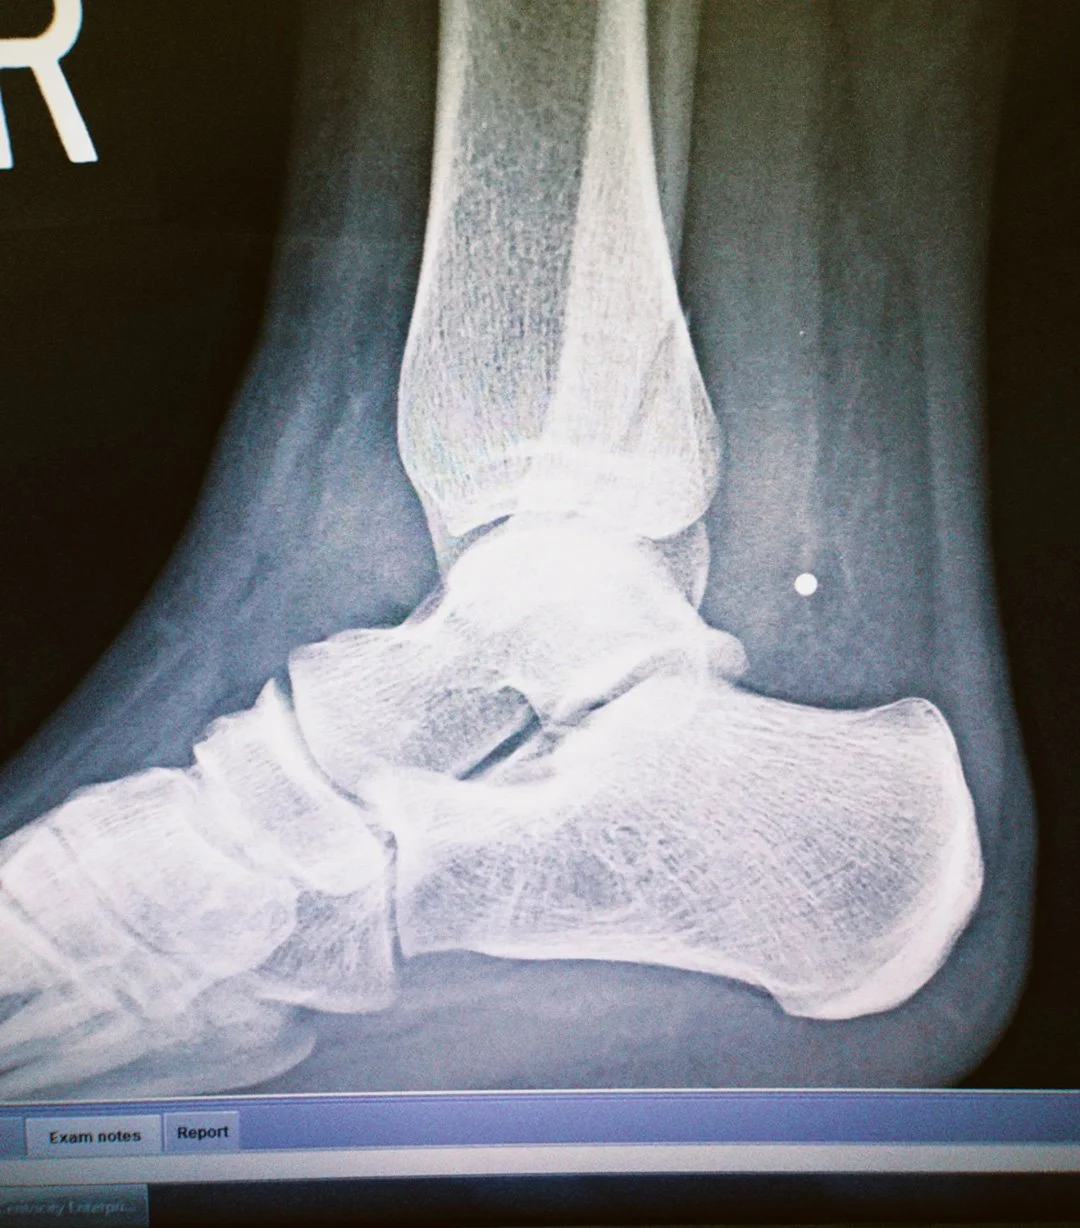

my x-ray, 2 days before leaving | 2019

I was seventeen, the dancing queen, prancing around Europe with one good foot and soaking up as much as I could. Would you believe me if I told you I broke my foot by slipping on a puddle running toward a pop fly at a co-ed softball practice two days before I left for Europe? Yes, that ACTUALLY happened. How did I prevail you ask? Lots of ibuprofen and stuffing my face with crepes and croissants. Rubbed some dirt on it and got back on the horse. Broken bones can wait, I need my close up in front of the Eiffel Tower!